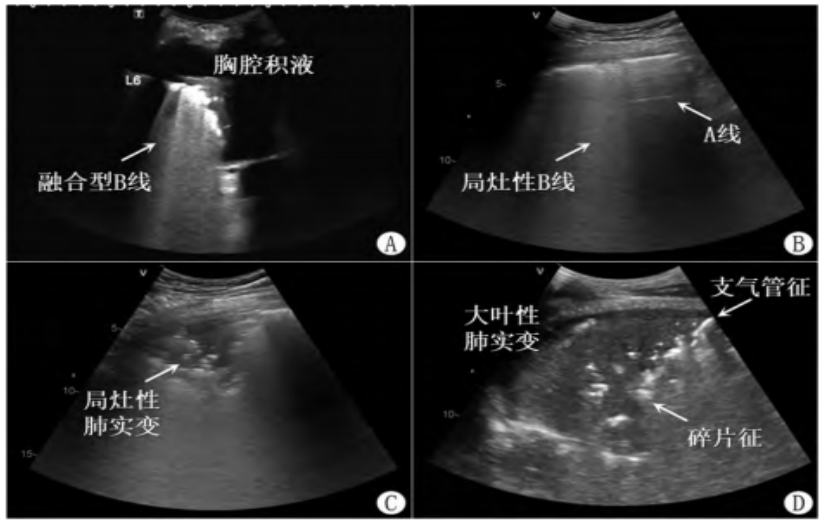

了解一下肺炎常见的几种超声征象。图8A为局部肺泡炎性渗出,可见少量胸腔积液,在正常肺和病变肺之间有一些融合的B线,局部有小实变。图8B为局灶性肺炎:B线与A线并存,被称为气液往返征,即靠近胸膜的一些炎性渗出可能并没有阻塞气道,支气管是通畅的,当吸气时,此处的含气就恢复了,我们看到的是A线;当呼气时,气体被排出,可能就出现了B线,这是靠近胸膜的小范围肺炎的征象。在临床中,如果患者的肺部超声一直表现为A线征象,病程中如果出现B线,且存在病情变化,如发热等,则应警惕医院获得性肺炎(HAP)的可能。图8C为炎性渗出不均匀,胸膜下局部小范围的肺泡塌陷呈实变征象,这是肺炎经典的碎片征。图8D为大范围肺叶炎性渗出呈实变的征象。其中点状、条状征象就是动态支气管充气征,说明气管相对通畅,可以看到有气流进出,在正常肺和异常肺的交界处可以看到碎片征。军团菌肺炎患者就会出现典型的大叶性肺肺炎实变。

图片

图8  肺炎典型超声表现